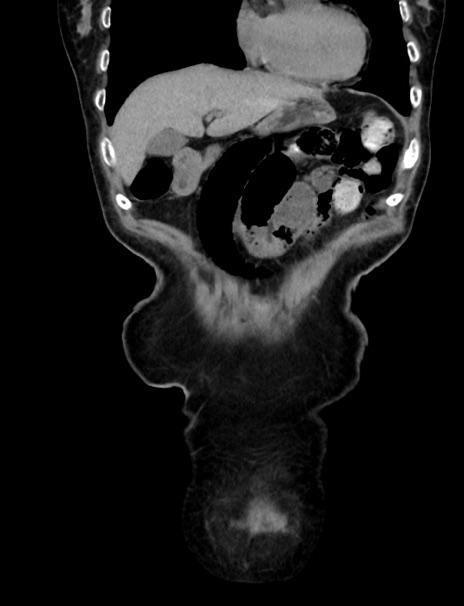

症例33(冠状断像)

【症例】70歳代 女性

【主訴】心窩部痛

【現病歴】延髄病変の精査・加療にて神経内科入院中。本日より心窩部痛あり。

【既往歴】虫垂炎

【身体所見】右下腹部を中心に圧痛と反跳痛あり。

【データ】WBC 10900、CRP 0.02